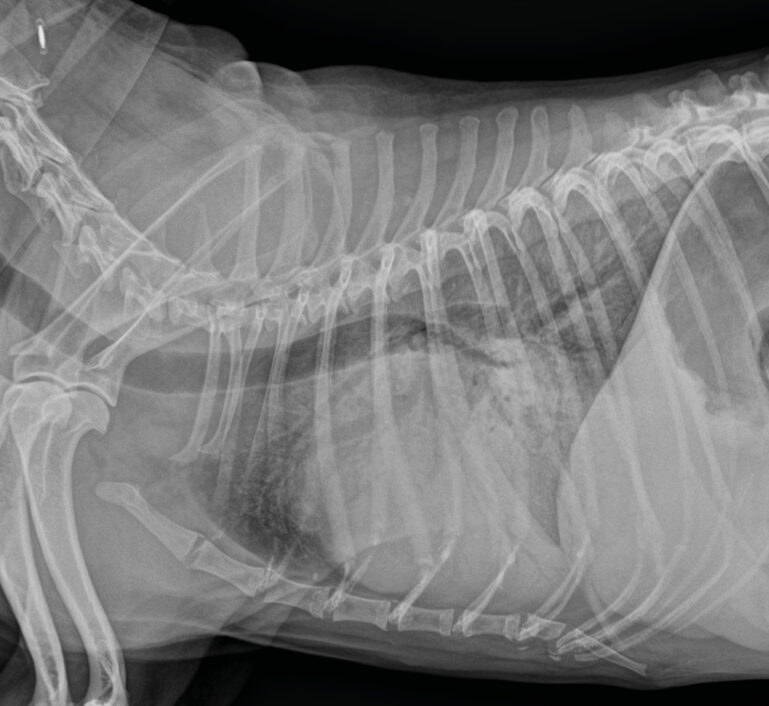

Radiografía de tórax latero-lateral derecha que muestra un aumento marcado la silueta cardiaca y un intenso patrón alveolar e intersticial pulmonar compatible con insuficiencia cardiaca congestiva izquierda.

Imagen 1. Radiografía de tórax latero-lateral derecha que muestra un aumento marcado la silueta cardiaca y un intenso patrón alveolar e intersticial pulmonar compatible con insuficiencia cardiaca congestiva izquierda.

Se pauta furosemida 4 mg/kg intravenosa/4 h. Tras dos horas se realiza una radiografía torácica, donde se aprecia un patrón intersticial y alveolar, además de cardiomegalia (imagen 1).